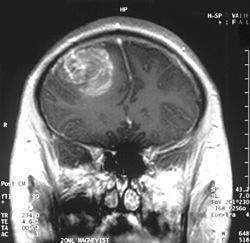

Fue descrito por primera vez en 1959 en el hospital Hôtel-Dieu de Québec, Canadá, por los doctores Jacqes Turcot, Jean Paul Després y François St. Pierre. Ellos reportaron dos casos del síndrome, en el cual dos hermanos (hombre y mujer) lo padecían. El hermano, de 15 años, consultó por diarrea y hematoquecia (deposiciones con sangre fresca). Le fueron hallados múltiples pólipos en el colon distal y en el recto, algunos de los cuales habían evolucionado a adenocarcinomas in situ. Le fue practicada una colectomía parcial y la resección en varias ocasiones de pólipos rectales. Fallece dos años después de la consulta inicial, y en la autopsia se halla destrucción completa de la médula espinal por causa de un meduloblastoma que la había infiltrado. La hermana, de 13 años, consulta por los mismos síntomas del hermano (diarrea y hematoquecia), y también le son encontrados múltiples pólipos en el colon distal y en el recto. Se le realizan dos colectomías para la extracción final de todo el colon, y le son destruidos periódicamente pólipos en el recto. Ocho años después de la consulta inicial, la paciente es hospitalizada por hallazgos compatibles con un tumor cerebral, falleciendo días después. La autopsia revela la presencia de un glioblastoma multiforme en el lóbulo frontal izquierdo (cerebro).

El diagnóstico del síndrome de Turcot se consigue a partir de la historia del paciente, una detallada evaluación clínica y algunas pruebas especiales. Dado que los niños con alguno de sus progenitores afectados tienen un riesgo de desarrollo de la enfermedad, se aconseja un examen sigmoidoscópico regular hasta la edad de 35 o 40 años. En algunos casos, las pruebas del ADN permiten detectar miembros de una familia que son candidatos a padecer la enfermedad. La radiología también permite detectar la presencia de pólipos intestinales, y también la presencia de algún tumor cerebral.

El tratamiento del síndrome de Turcot está enfocado para paliar los síntomas de cada individuo. La eliminación quirúrgica de los pólipos del recto y del colon (proctocolectomía) puede prevenir la aparición de malignidades. Sin embargo, si se lleva a cabo una ileoproctostomia, los pólipos rectales pueden regresar. En algunos pacientes el rápido desarrollo de nuevos pólipos puede aconsejar una ileostomía o incluso una anastomosis ileoanal. Todos los pacientes afectados deben ser examinados neurológicamente a intervalos regulares para detectar cuanto antes la presencia de un tumor cerebral. El tratamiento de este dependerá de su tipo, localización y tamaño y consistirá cirugía acompañado de radio y/o quimioterapia.